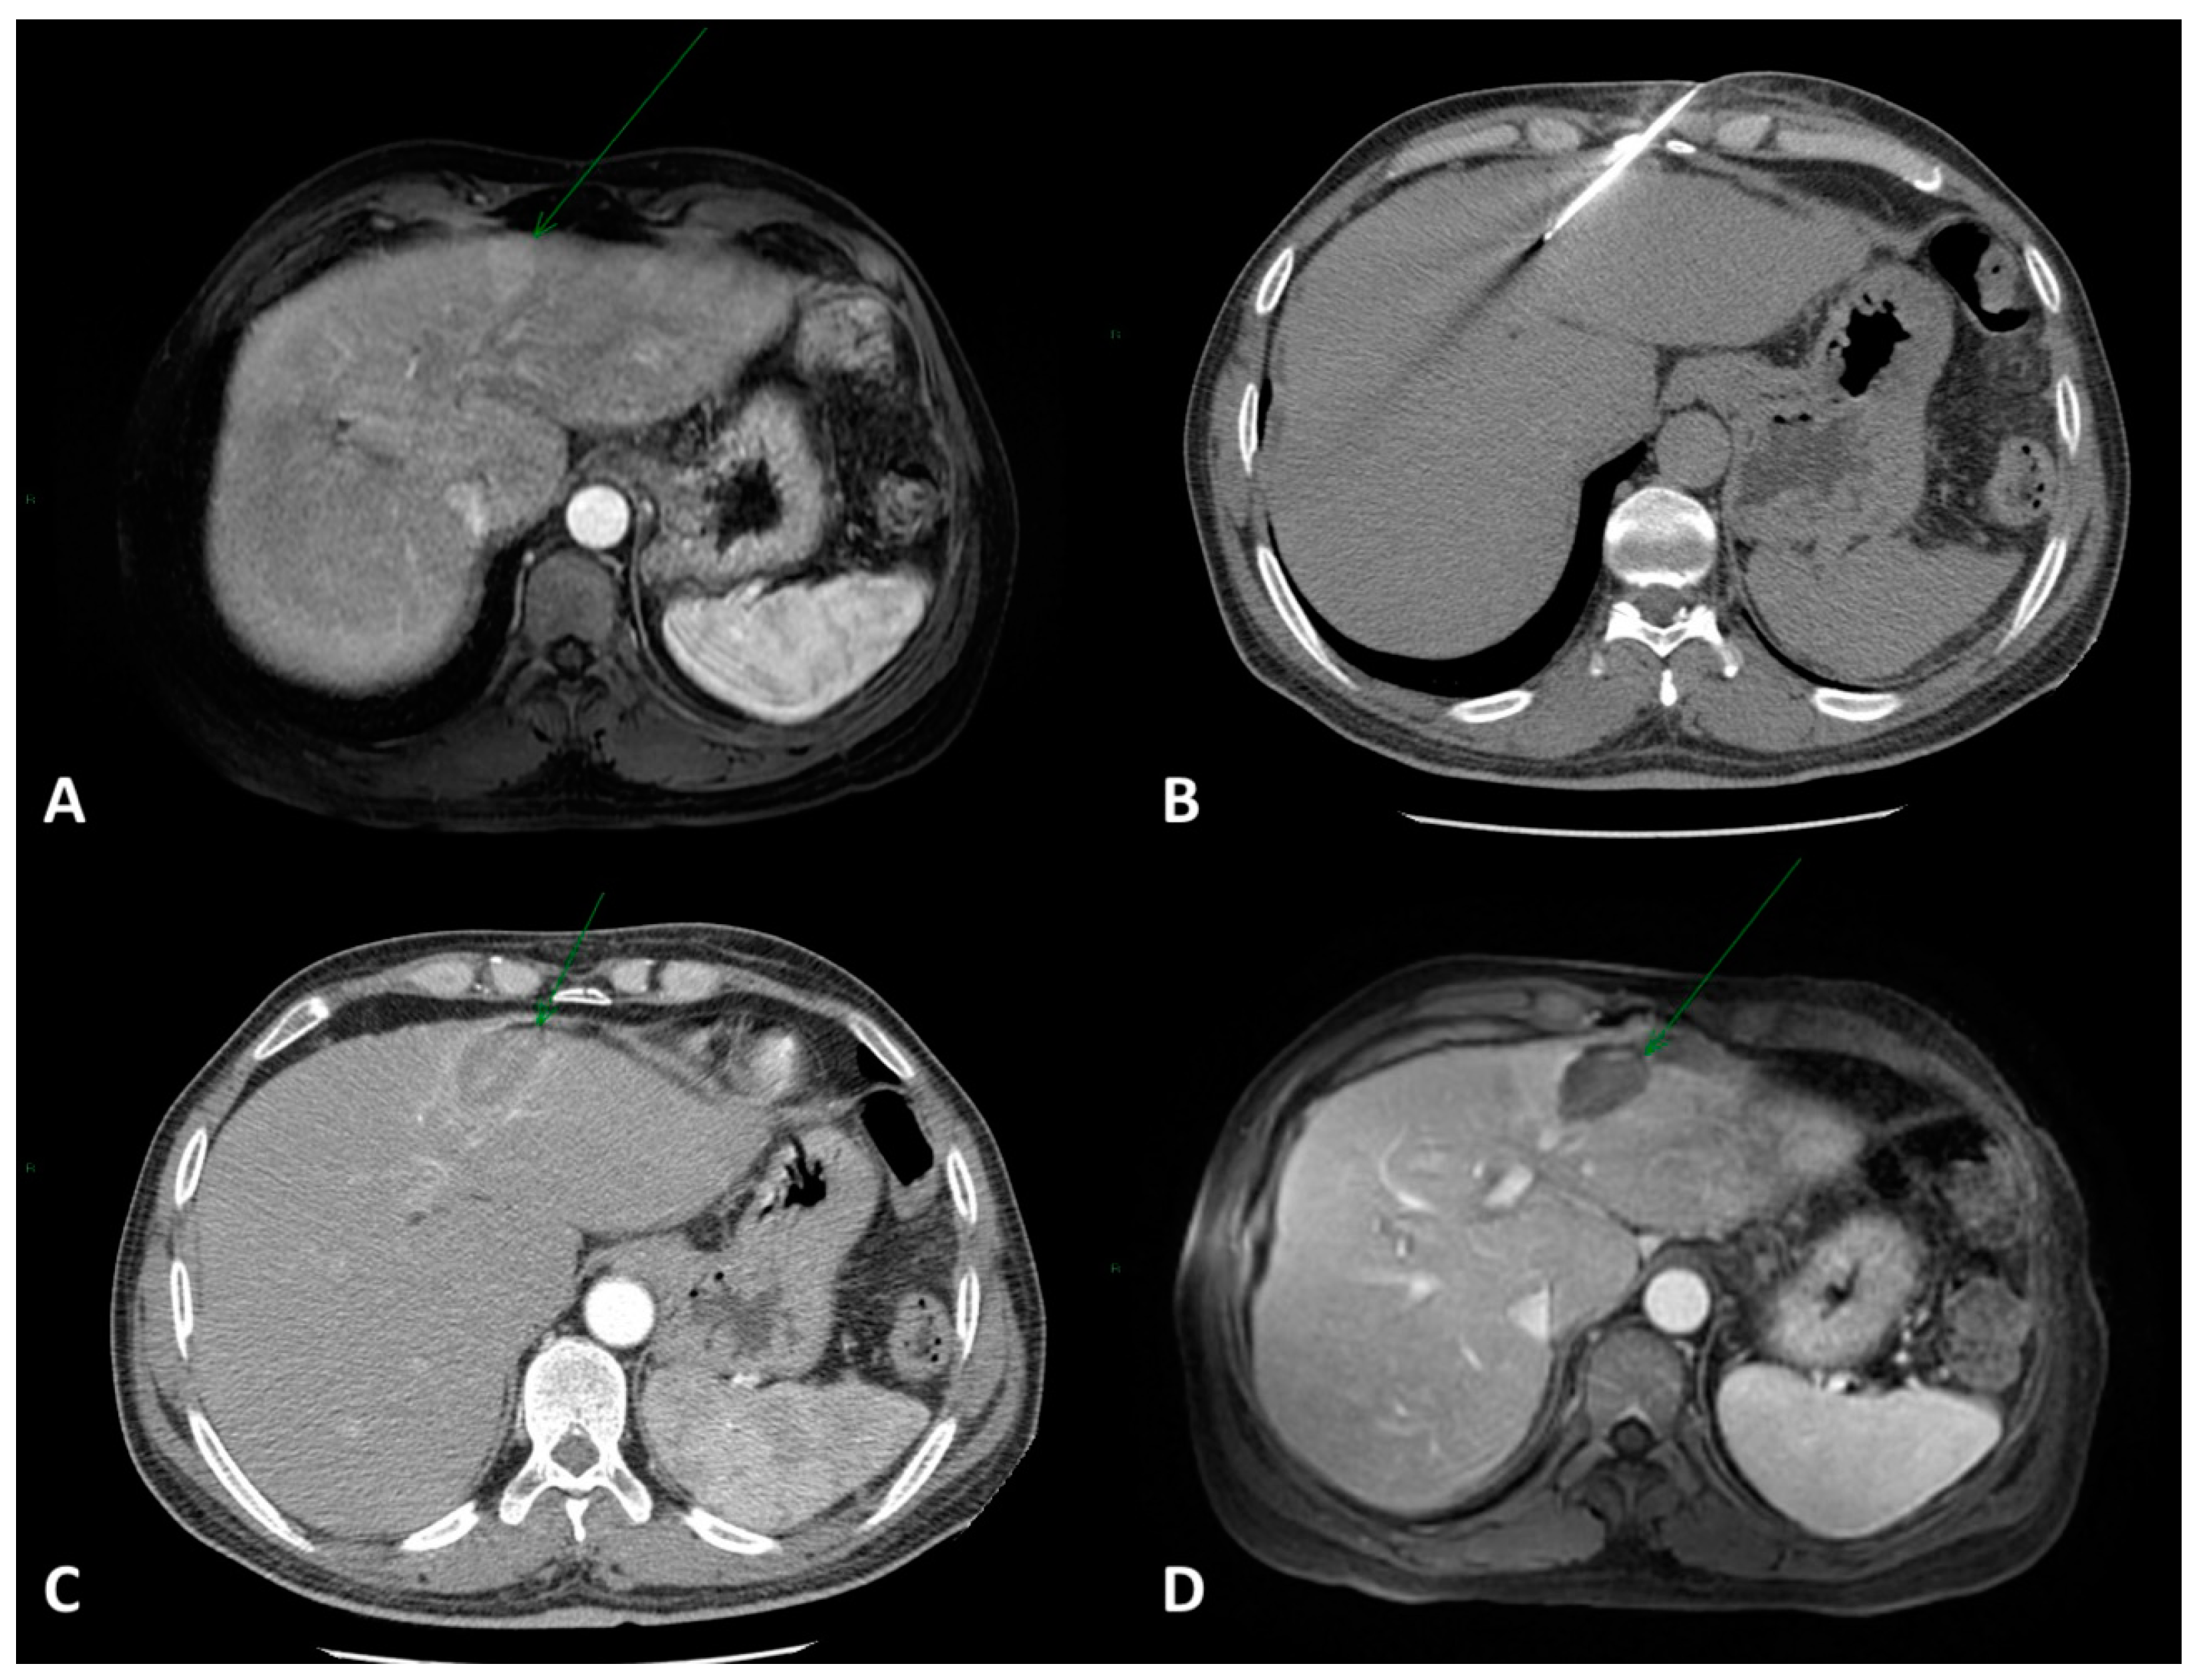

2. Local Ablation

2.1. Eastern Perspective

2.2. Western Perspective